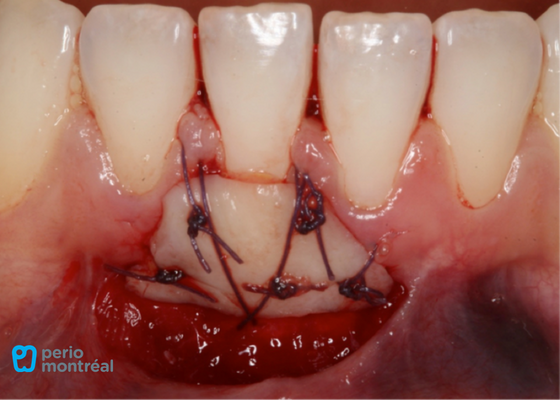

Graft Sutured at Recipient Site, Palate Treated with a Hemostatic Agent and Sutured